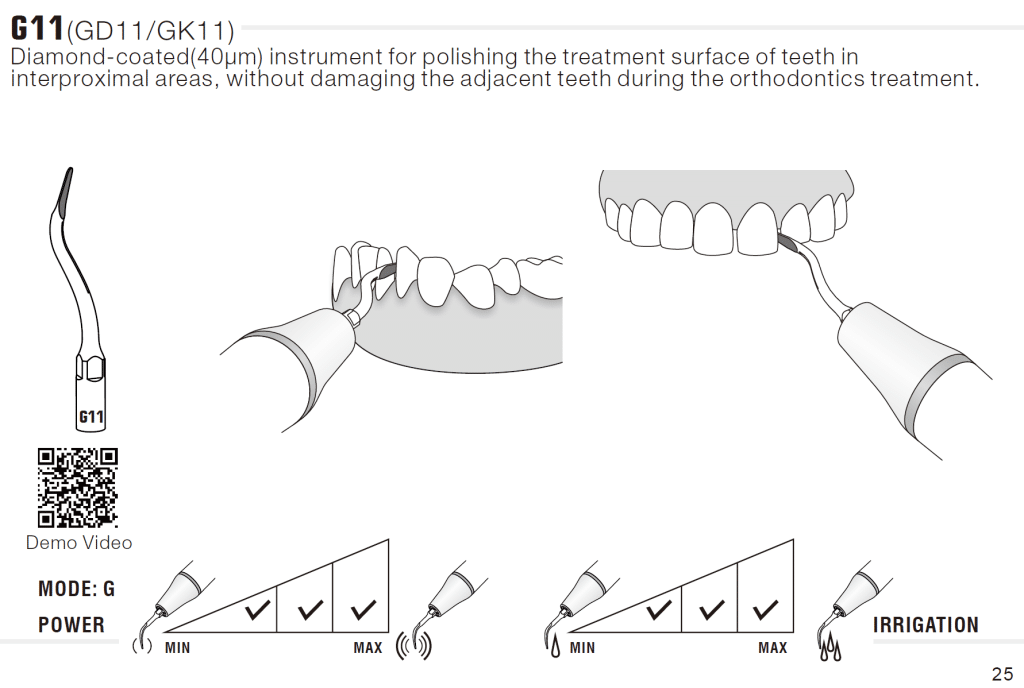

Surface treatment protocol for the E-max

- Sandblasting of the internal surface

- Etch the internal surface of E-max with 10% HydroFloric acid etchant for 20-25 seconds

- Etch the internal surface of E-max with 37% Phosphoric acid etchant for 20-25 seconds

- Silane coupling agent for 60 seconds then air dry